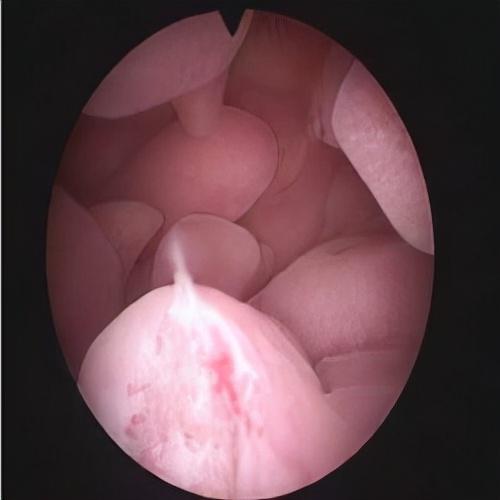

在顺义妇儿医院妇科门诊,经常会有患者问到关于子宫内膜息肉的各式各样的问题。妇二科副主任医师纪翠红指出,子宫内膜息肉是一种常见的妇科疾病,多见于35岁以上女性,随年龄增长发病率也增高。我国女性息肉发病率24-25%,还是非常高的。子宫内膜息肉是子宫局部内膜过度生长造成的,可单个或多个,可小也可大。

3.对于有异常出血症状,或者有息肉的不孕患者考虑手术治疗,不建议盲目刮宫,容易漏诊,复发及息肉破碎,影响病理检查。建议宫腔镜息肉切除术。息肉切除后可以提高怀孕机率。